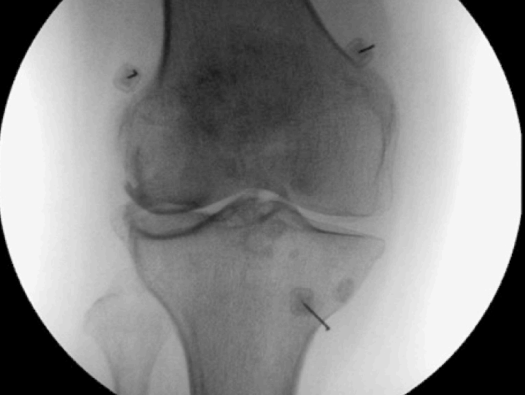

The procedure is done in operation theatre under local anesthesia. The patient is made to lie on the operation table and the appropriate joint/ spine is identified under imaging guidance. RF needle is inserted under imaging guidance to target the concerned nerve and thereafter RFA is performed using RF machine

Knee joint

- RFA genicular nerve